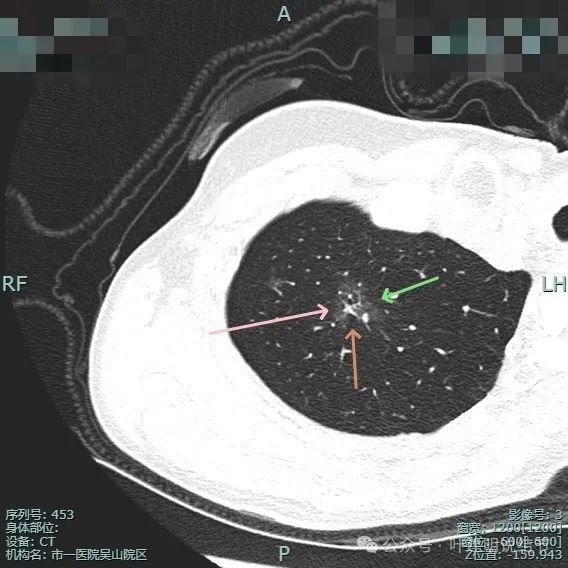

血管进入、表面分叶、胸膜牵拉、磨玻璃成分明显、实性部分缺乏收缩力但显杂乱,整体轮廓与边界清。

实性成分较多,表面不平,磨玻璃部分较淡,血管进入与穿行,胸膜牵拉可见,距其不远有次病灶也是淡磨玻璃密度,轮廓较清,也考虑是肿瘤范畴的,当然风险仍低。